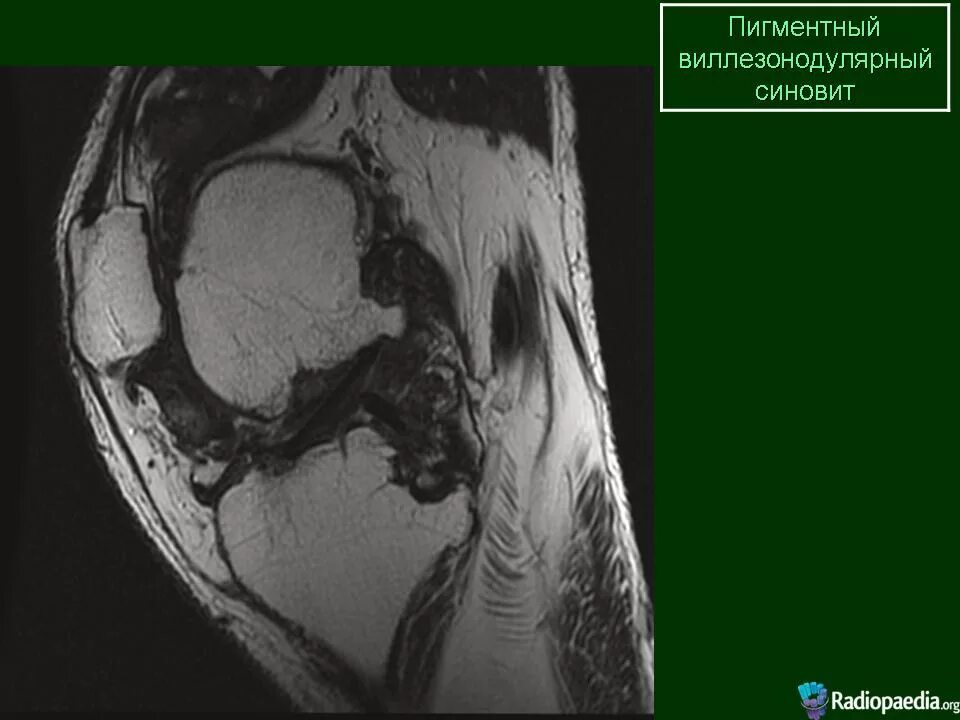

Пигментный виллонодулярный синовит